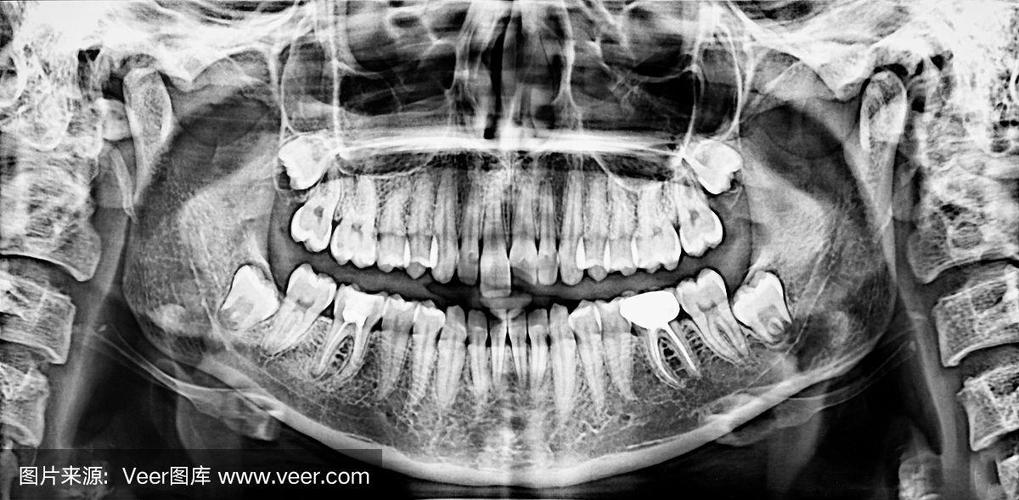

全景片(Panoramic Radiograph / Panorex / Orthopantomogram, OPG)

- 目的: 一次性显示全口牙列、上下颌骨、上颌窦、颞下颌关节、部分鼻腔和咽部,是口腔科最常用的口外X线片。

- 拍摄方法: 患者站立或坐姿,下颌置于额托,咬住定位杆,头部固定于机器中,X线球管围绕患者头部旋转,探测器在另一侧同步旋转接收信号。

- 应用:

- 口腔全面检查(龋齿、牙周炎、残根、多生牙、埋伏牙)。

- 评估牙槽骨状况(种植术前评估)。

- 观察颌骨囊肿、肿瘤、骨折。

- 评估正畸病例(牙齿排列、颌骨关系)。

- 观察阻生智齿的位置。

- 特点: 视野大,效率高,辐射剂量相对较低(比CBCT小很多),但影像有几何变形和放大,细节不如根尖片清晰,对根尖周细小病变显示不佳。